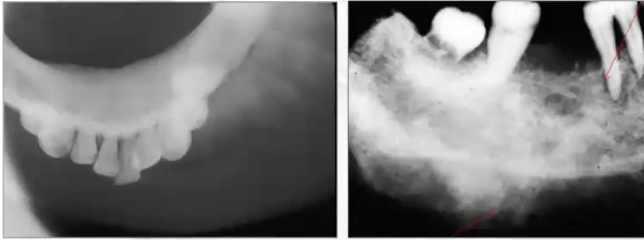

What is this pano showing?

Expansion, subtle sunburst appearance, spiking resorption of 1st molar; seen in osteosarcoma

What is this PA showing?

Widening of PDL seen in osteosarcoma

What is this PA showing?

Calcification filling the sinus, widened PDL, spiked appearance of roots seen in osteosarcoma